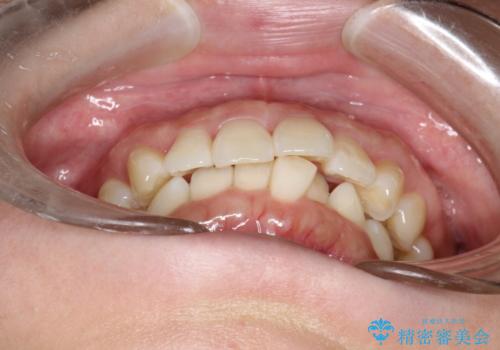

インビザライン ライトパッケージによる部分矯正治療 下の前歯のみの歯並び改善

- インビザライン ライトパッケージパーシャル(下顎のみ)

- 下の前歯の歯並びのみの改善をご希望されました。

インビザライン ライトパッケージ下顎のみ(1枚~14枚まで)での治療を行なっていきました。

マウスピース枚数 初回14枚 + 追加13枚

概ね7ヶ月で治療完了しました。

インビザラインのライトパッケージでは14枚までという枚数制限がありますが、限られた枚数の中で当院独自の工夫を随所に盛り込み、狙い通りの治療結果が得られました。